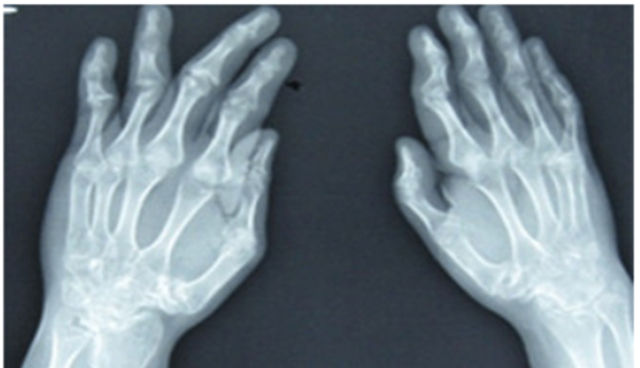

在线咨询每位备受风湿性关节炎疾病折磨的患者一定都会知道该疾病的危害,为了及早的控制住这种疾病,患者需要做到早发现早治疗,在疾病早期进行治疗的话,治疗的效果会好,随着医学技术的不断进步,治疗风湿性关节炎的方法是越来越多,较为常见的方法包括一般疗法、局部疗法、饮食疗法以及针灸疗法,这几种治疗方法的效果都是很不错的,患者可以进行选择,下面我们就来进行一下详细的介绍,希望可以帮到大家。